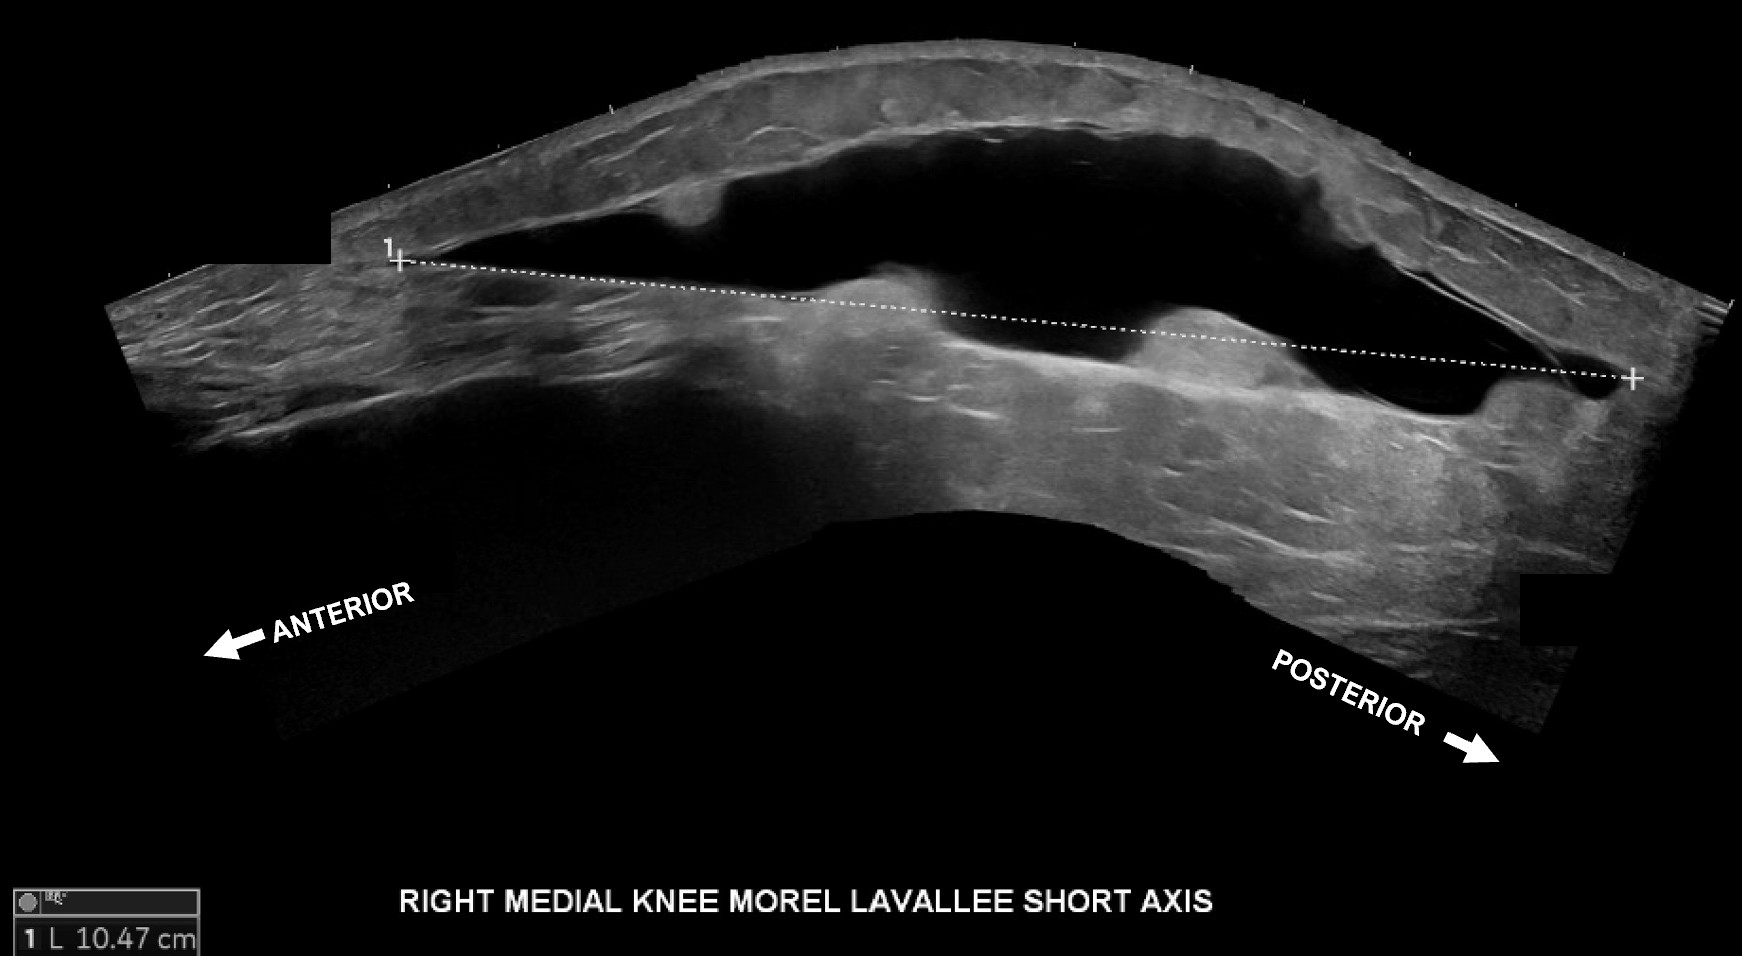

Labeled short axis extended view of the medial distal thigh and knee with evidence of a Morel-Lavallee lesion between the skin and superficial fat and the fascia and deep fat measuring approximately 10.5 cm from anterior to posterior.

Unlabeled short axis extended view of the medial distal thigh and knee with evidence of a Morel-Lavallee lesion measuring approximately 10.5 cm from anterior to posterior.